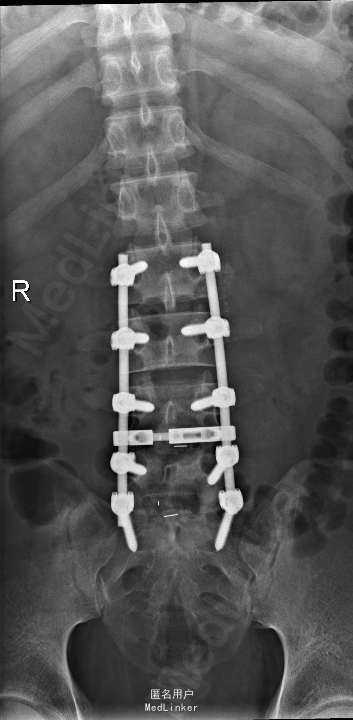

查体:腰部叩痛,腰部活动受限,左侧膝内侧、小腿外侧、内踝、足部感觉减退,右侧小腿、足背感觉减退,屈髋、伸膝、踝背伸肌肌力左侧4级,右侧4-5级,踇背伸、跖屈肌肌力左侧3-4级,右侧4级,双侧膝腱反射+,跟腱反射+,双侧巴氏征阴性,直腿抬高试验左侧40°阳性,右侧阴性。 辅助检查: X-ray:腰椎退行性变,多节段不稳 CT:腰椎间盘突出并椎管狭窄伴钙化,腰2-3,3-4,4-5,腰5骶1 MR:腰椎间盘突出并椎管狭窄,腰2-3,3-4,4-5,腰5骶1 上传受限无法全部上传,见谅

诊断:腰椎间盘突出症并椎管狭窄 处理:1、完善相关辅助检查,明确诊断,有无手术指证; 2、完善手术评估,有无手术禁忌,手术风险及并发症; 3、在全麻下行腰椎后路多节段减压椎间植骨融合内固定术 4、腰2-3,腰3-4行开窗减压,腰4-5,腰5-骶1行椎间Cage植骨融合

随访:1、应常规术后1个月、3个月、半年随访; 2、术后患者腰痛较前减轻,下肢麻木感觉较前好转,下肢活动较前有力,屈髋、伸膝、踝背伸肌肌力左侧4级,右侧4-5级,踇背伸、跖屈肌力左侧4级+,右侧4-5级,左侧肢体抬高试验阴性。 讨论:1、多节段腰椎间盘突出,手术指证把握 2、责任节段的确立,以影像学间盘突出节段为依据,还是联系临床表现? 3、手术节段的确立,以影像学与临床表现确立责任节段间盘为依据,还是术中探查为金标准? 4、多节段间盘突出,开窗髓核VS椎间植骨融合? 5、开窗髓核与椎间植骨融合相结合,如何确定融合节段与开窗节段? 6、多节段内固定,腰椎活动度影响,稳定与腰椎活动功能的平衡?